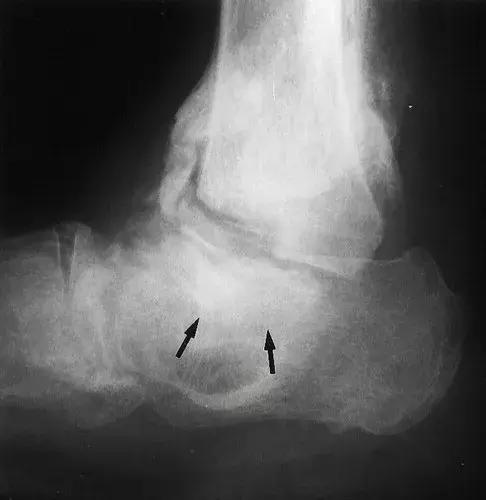

图16:60岁女性糖尿病人,胫骨关节的神经性骨关节病。侧位X线片显示胫骨远端和距骨(箭头)的再吸收和碎裂,明显的硬化,骨赘和骨膜炎(箭头)。